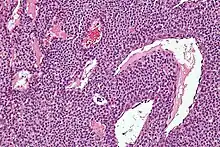

| Micrograph of a glomus tumor. H&E stain. | |

Histologically, glomus tumors are made up of an afferent arteriole, anastomotic vessel, and collecting venule. Glomus tumors are modified smooth muscle cells that control the thermoregulatory function of dermal glomus bodies. As stated above, these lesions should not be confused with paragangliomas, which were formerly also called glomus tumors in now-antiquated clinical usage. Glomus tumors do not arise from glomus cells, but paragangliomas do.

By histopathology, glomus tumors can be termed as follows:[7]

- Solid glomus tumor (75% of cases): Consisting predominantly of glomus cells, with poor vasculature and rare smooth muscle cells.

- Glomangioma (20% of cases): Tumors with a prominent vascular component.

- Glomangiomyoma (5% of cases): Tumors with prominent vascular and smooth muscle components.